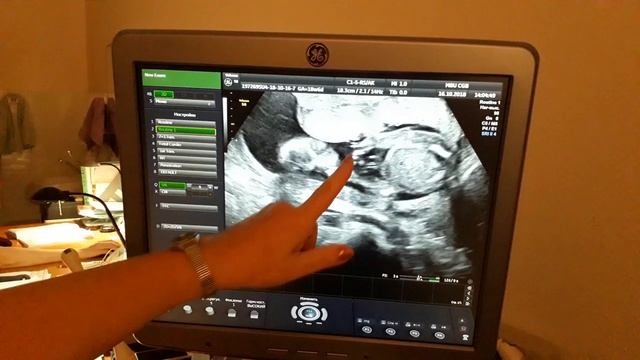

ПЕРВОЕ УЗИ ВО ВРЕМЯ БЕРЕМЕННОСТИ | Нормы показателей УЗИ по неделям беременности https://youtu.be/1GRMbJgJhN0 Первое плановое УЗИ, которое рекомендуется всем будущим мамочкам, проводится на сроке с 10 до 13 недель включительно. Это важный и информативный для врачей и женщин первый пренатальный скрининг. Теоретически, первое УЗИ может быть информативным при беременности уже через 3 недели после предполагаемого дня овуляции. Это соответствует примерно пятой акушерской неделе. На этом сроке впервые появляется техническая возможность увидеть на мониторе ультразвукового сканера плодной яйцо, что будет свидетельствовать о наступившей беременности. Но до 10-11 недели УЗИ-диагностика официально не рекомендуется без веских на то показаний. #УЗИ #беременность #первоеУЗИ